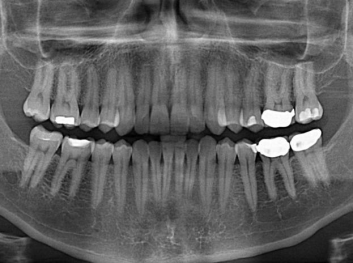

在體外測試中,材料刺激干細胞進入牙本質的增殖和分化速度,促進形成牙齒骨組織。研究人員認為,一旦材料在受損牙齒中應用,這些干細胞可以自動修復來自填充物上的損壞。在本質上,該生物材料將使牙齒自愈。

在未來,Adam Celiz說,可再生材料能制成各種填充物以便受損牙齒的自身治愈,降低補牙失敗率,甚至會消除大部分人對根管治療的需要。